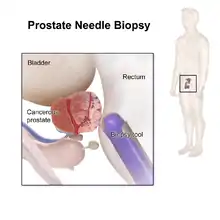

Several other tests can be used to gather information about the prostate and the urinary tract. Digital rectal examination may allow a doctor to detect prostate abnormalities. Cystoscopy shows the urinary tract from inside the bladder, using a thin, flexible camera tube inserted in the urethra. Transrectal ultrasonography creates a picture of the prostate using sound waves from a probe in the rectum, but the only test that can fully confirm the diagnosis of prostate cancer is a biopsy, the removal of small pieces of the prostate for microscopic examination.

Biopsy

If cancer is suspected, a biopsy is offered expediently. During a biopsy, a urologist or radiologist obtains tissue samples from the prostate via the rectum. A biopsy gun inserts and removes special hollow-core needles (usually three to six on each side of the prostate) in less than a second. Prostate biopsies are routinely done on an outpatient basis and rarely require hospitalization.

Antibiotics should be used to prevent complications such as fever, urinary tract infections, and sepsis[81] even if the most appropriate course or dose is undefined.[82] About 55% of men report discomfort during prostate biopsy.[83]